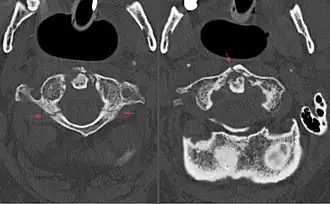

В диагностике переломов Джефферсона используют рентгенографию, компьютерную и магнитно-резонансную томографии. На рентгенограммах определяется смещение боковых масс атланта кнаружи[7]. Компьютерная томография даёт возможность оценить изменения костных структур, в то время как магнитно-резонансная томография — мягкотканных[8].